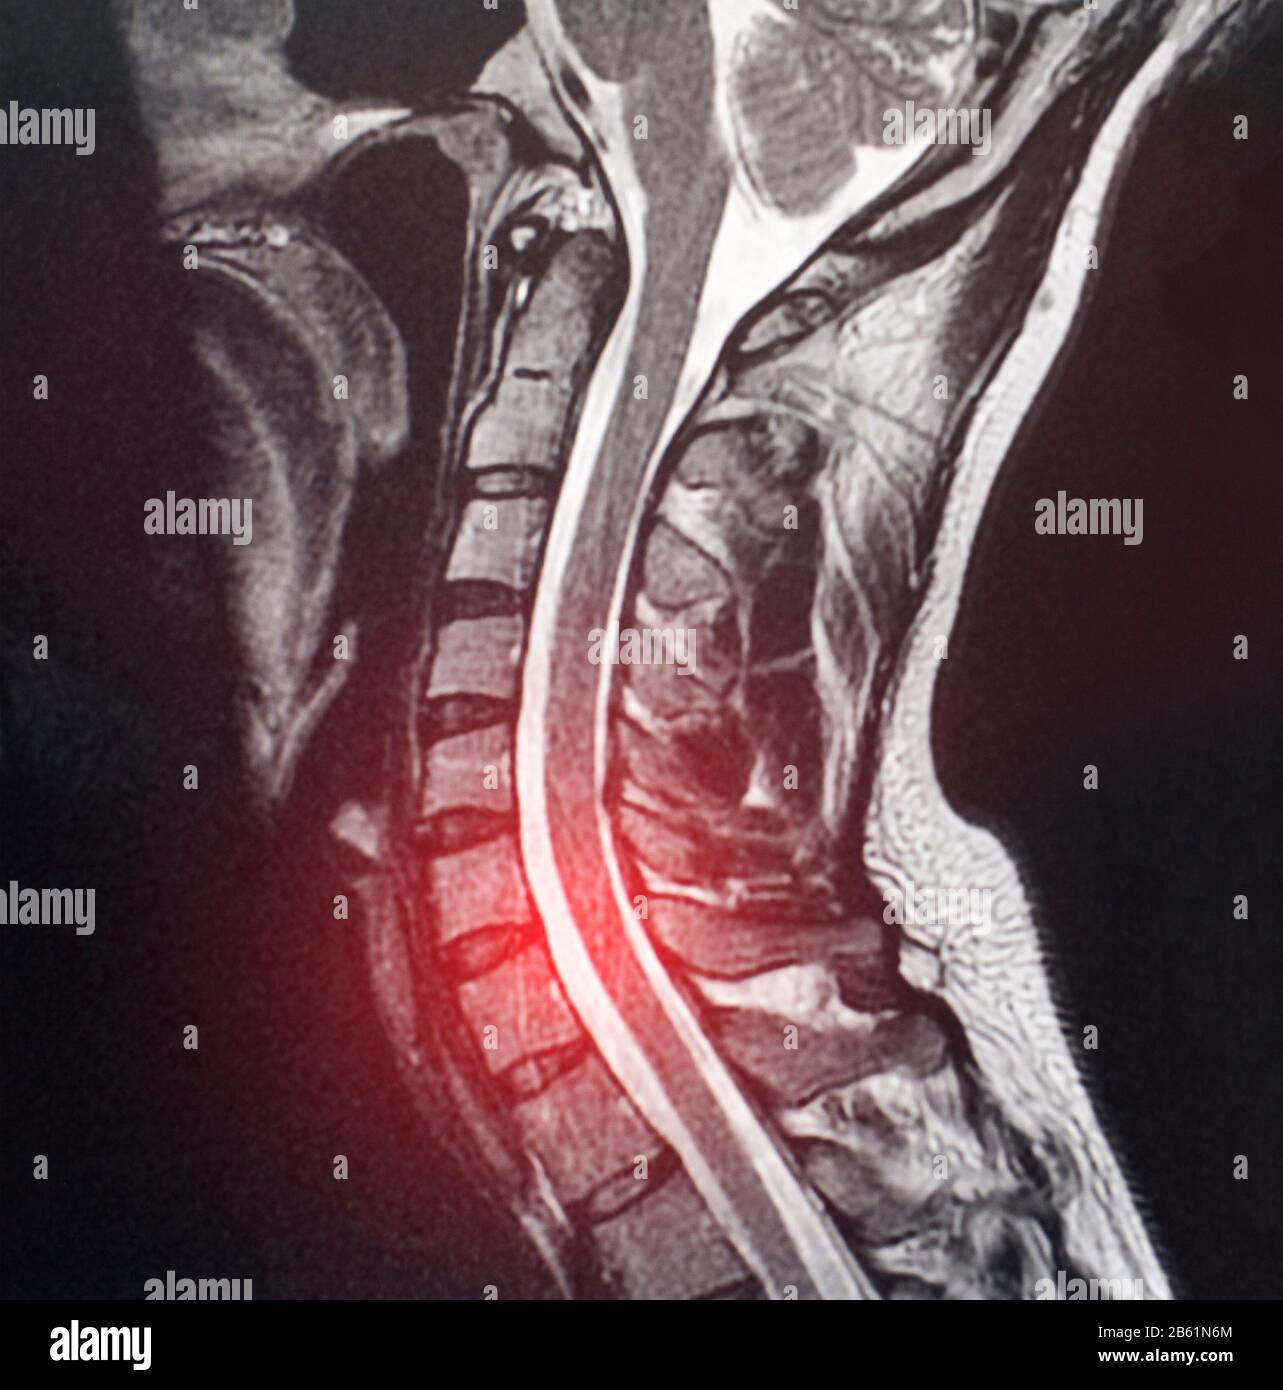

Ver Resonancia magnética de columna dorsal, plano sagital, en ponderación actualizar

Veamos MRI De La Espina Dorsal Cervical - De Resonancia Magnética Fotos de popular

Ver Resonancia Magnética columna dorsal volviéndose viral

WebLa resonancia con contraste es un estudio de imagen para visualizar órganos y tejidos dentro del cuerpo. A diferencia de una resonancia magnética. WebLa columna vertebral, podría dividirse en tres partes: cervical, dorsal y lumbar. Los dolores en la zona lumbar son cada vez más frecuentes debido al sedentarismo y al ritmo de. WebLa columna cervical es la porción superior de la columna vertebral (espina dorsal) cuya función es sostener al cráneo. A diferencia de la columna lumbar y dorsal,. WebLa Resonancia Magnética de Tórax se puede llevar a cabo para: Brindar una alternativa a la angiografía o evitar la exposición repetida a la radiación; Aclarar hallazgos de. WebLa resonancia magnética se utiliza para evaluar o detectar: Anatomía y alineación de la columna. Defectos congénitos en las vértebras o la médula espinal. Lesión por trauma. WebLa resonancia magnética (RMI) es un estudio completamente confiable y sin ningún tipo de dolor. Permite visualizar imágenes de los órganos, huesos y tejidos a. WebUna resonancia magnética del tórax proporciona imágenes detalladas de los tejidos dentro de la zona torácica. En general, no es tan buena para revisar los pulmones como una. WebLa resonancia magnética (RMI) es un método de estudio para producir imágenes detalladas de órganos y tejidos a través de un campo magnético y ondas de.